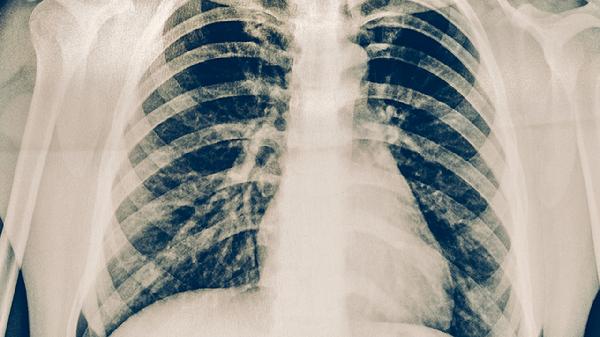

治疗期间应保持每天2500毫升饮水,适量补充鸡蛋、瘦肉等优质蛋白。室内定期通风消毒,咳嗽时用肘部遮挡。每月需复查胸部CT观察病灶吸收情况,完成疗程后仍需随访2年。注意与家人分餐饮食,密切接触者应进行结核菌素皮肤试验筛查。出现持续低热或痰中带血等症状需及时复诊。